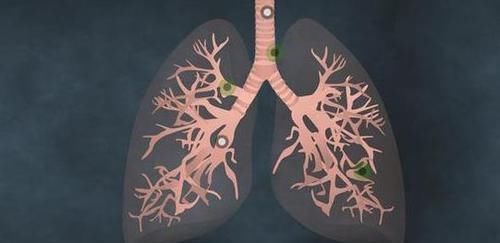

●身体长期处于低热:

日常生活中,如果你的身体长期处于不明原因的低热状态,看起来也不像是高热发烧,甚至有些患者的手指还会出现变形问题,这些情况都是在暗示你肺癌的风险。身体之所以会出现低热问题,是由于患者体内的肿瘤细胞在不断坏死的过程中,会释放出大量的热量,从而导致患者体温出现不明原因的低热情况。